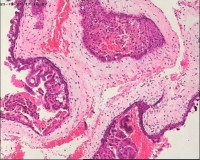

性别

女

年龄

20岁

临床诊断

一般病史

停经3月,阴道不规则流血7天。

标本名称

宫刮物

大体所见

灰白灰红碎组织一堆,大小为7*6*1cm,部分组织呈水泡状

水肿的绒毛和蜕膜,没看到增生的滋养细胞。必要时可做IHC除外部分葡萄胎,并结合临床HCG。

考虑葡萄胎